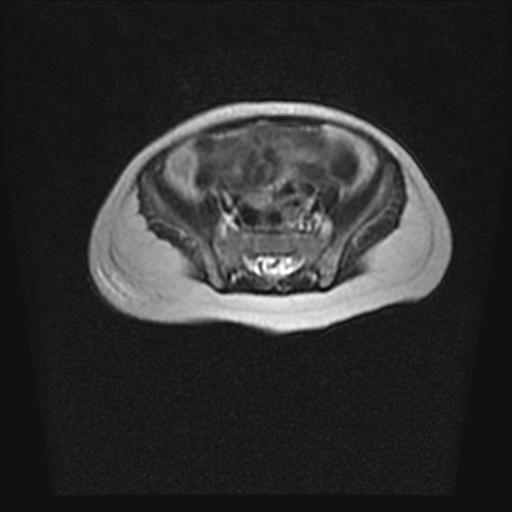

标题: PED0016:脊膜膨出 [打印本页]

标题: PED0016:脊膜膨出

四个月的女婴,ct示脊膜膨出.

脊柱裂、脊膜膨出,请结合临床除外皮毛窦。

脂肪脊髓脊膜膨出

脊柱裂、脊膜膨出